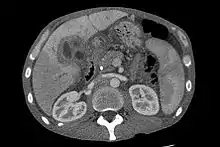

Abdominal imaging

CT scan showing cholangiocarcinoma

Ultrasound of the liver and biliary tree is often used as the initial imaging modality in people with suspected obstructive jaundice.[49][50] Ultrasound can identify obstruction and ductal dilatation and, in some cases, may be sufficient to diagnose cholangiocarcinoma.[51] Computed tomography (CT) scanning may also play an important role in the diagnosis of cholangiocarcinoma.[52][53][54]